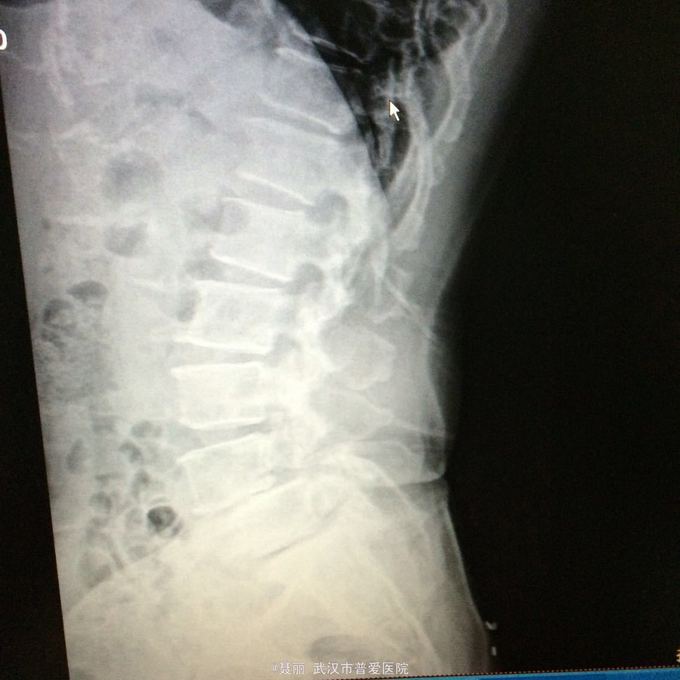

患者,女,51岁。 反复腰痛并间歇性跛行5年余,加重并左侧臀部2月余。 患者于5年前无明显诱因外伤诱因出现腰痛,不伴有双下肢麻木、乏力及间歇性跛行,卧床休息后好转,间歇发作,进行性加重。 既往史:有高血压病、糖尿病病史,否认有药物过敏

:L4/5棘突间轻压痛,叩痛,棘间左侧椎旁压痛;双下肢肌力、肌张力正常,病理反射未引出。 门诊资料:外院行腰椎CT检查示:L3-S1椎间盘膨出,L4椎弓崩裂并向前滑脱(重度)椎管狭窄。 入

入院诊断:、腰椎滑脱(L4/5 峡部裂性) 诊疗计划:1:完善有关检查2卧床休息,行改善微循环、3.腰椎后路复位减压植骨融合术

行改善微循环、3.腰椎后路复位减压植骨融合术 腰椎滑脱(L4/5 Ⅱ度)、腰椎管狭窄症(L3/4)、腰椎间盘突出症(L5/S1)查体双下肢感觉、活动无明显异常。双下肢末梢血液循环可。换药见伤口对合良好,无明显红肿渗出。伤口已拆线。嘱加强双下肢活动及功能锻炼,避免下肢深静脉血栓,主动及被动四肢活动,预防血静脉及床褥形成,加强腰背肌锻炼,适量康复功能锻炼。一个月后来复查伤口愈合好,疼痛没有,活动可